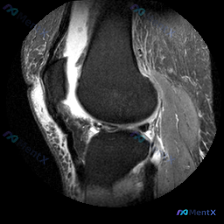

今天遇到一个很有代表性的情况:用户提供了一张膝关节矢状位MRI,主诉提示「半月板异常」,但我们阅片后发现结果和预期完全不一样,整理出来给大家讨论。 基本影像信息 这是一张膝关节矢状位质子密度或T2加权MRI,图像清晰度良好,信噪比适中,没有明显运动伪影,解剖结构显示清晰,层面大致位于膝关节中部区域。...

刚整理了一份膝关节MRI读片病例,分享一下完整分析思路。 病例影像基本信息 这是一张膝关节MRI矢状位图像,用户提问是否存在半月板异常,我们来一步步分析: 影像基础评估结果 1. 骨骼与关节: 股骨远端、胫骨近端皮质连续,无明显骨折,无明显骨髓水肿、软骨下囊肿,关节间隙和对合关系基本正常 2. 关节...